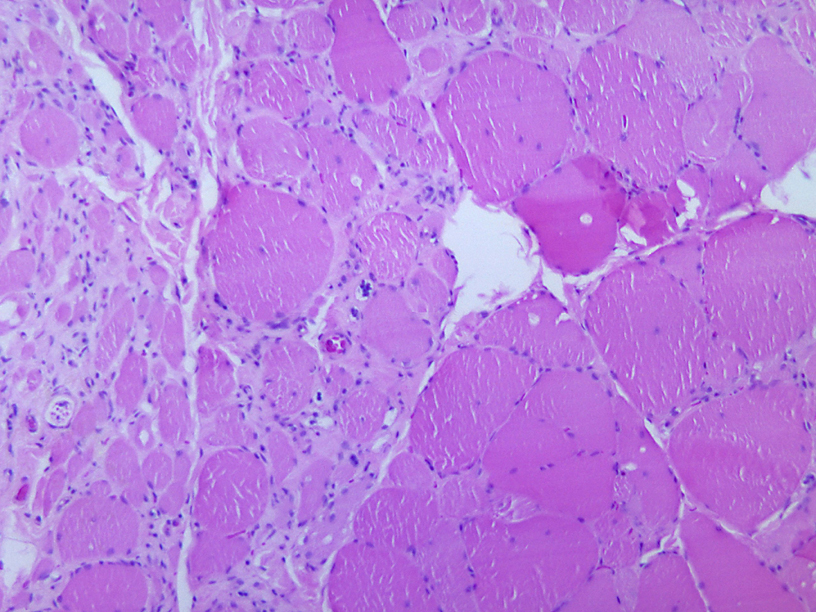

Poliovirus_Myotonic_dystrophic_changes

Дистрофические изменения в мышечной ткани. вызванные полиомиелитом. Источник: Wikimedia Commons